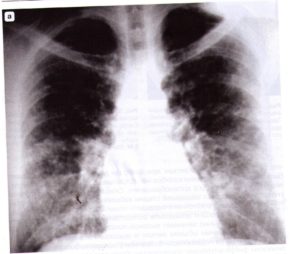

• Рентгенологическое исследование •• При остром ГП изменения в лёгких выявляют в 30–49% случаев (часто изменчива) ••• Диффузная интерстициальная инфильтрация с затемнением базальных отделов ••• Нежные округлые тени размером от 1–3 мм и более ••• Усиление и деформация лёгочного рисунка ••• Пневмофиброз •• При хроническом ГП ••• Усиление лёгочного рисунка, двусторонние пятнисто-очаговые или узелковые инфильтраты ••• При прогрессировании болезни — диссеминация процесса ••• Прикорневая лимфаденопатия, плевральный выпот или пневмоторакс не характерны ••• В 40–50% случаев в верхних долях превалируют округлые тени и бронхоэктазы.